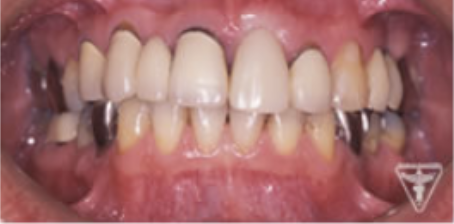

治療前

初診時の正面観・側方観・かみ合わせの面の状態を示します。

下の顎のずれがあるのを確認して下さい。